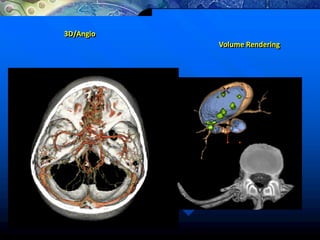

3D/Angio

Volume Rendering MPVR/MIP

Volume Rendering